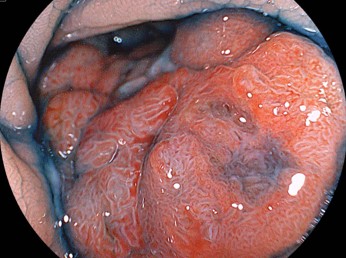

症例2:便潜血検査2回法で、2回陽性で受診。SD junction(S状結腸と下行結腸の境界)に腫瘍サイズ30mmの大型の有茎性(くきを有する病変)の隆起性病変を認め、日帰りにて内視鏡的粘膜切除術(EMR)で切除しました。

境界部に非常に存在する大型の腫瘍であったため、視野確保が困難でした。拡大内視鏡で、「がん」を疑うVI型ピットパターンを認めましたが、診断的治療目的で内視鏡的粘膜切除術(EMR)を施行しました。

一つの視野で全貌が追えないレベルの非常に太くて長い茎を有しているので、出血のリスクが高いのは内視鏡医なら即座に理解するでしょう。